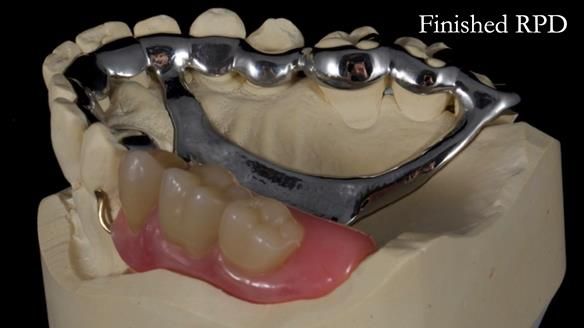

Welcome to Newsletter 64. I'll walk you through the process of providing a Mk 2 metal-based partial denture (RPD), for Ian a retired Veterinary Surgeon aged 78. The RPD was made at an increased vertical dimension and acted as an occlusal stabilisation splint - reducing the wear and bite force on the remaining natural teeth.